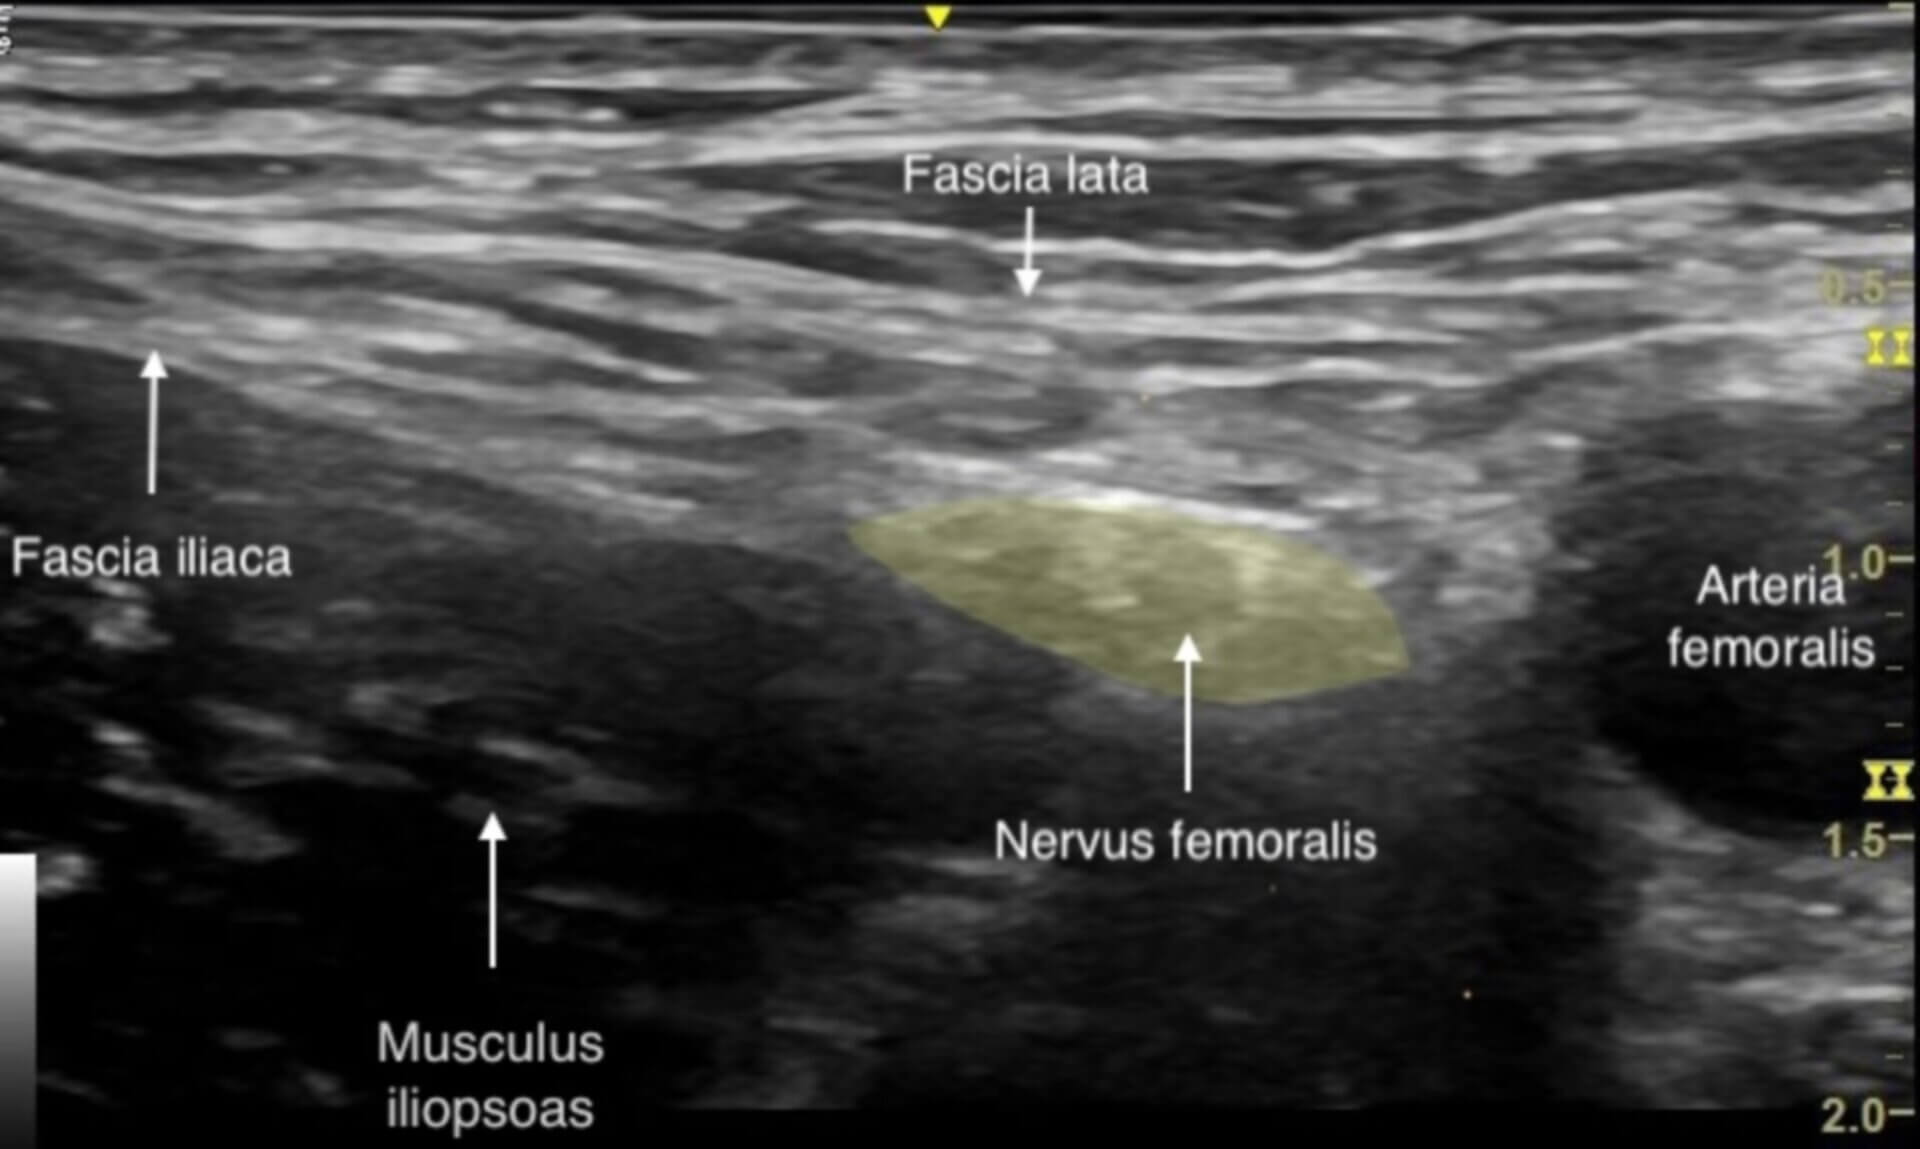

Der Femoralisblock ist ein peripheres Regionalanästhesieverfahren, bei dem durch die Injektion eines Lokalanästhetikums der Nervus femoralis blockiert wird. Die Punktion erfolgt in der Regel ultraschallgesteuert, z.B. in In-Plane-Technik. Hier ist beispielhaft der Nervus femoralis sonographisch dargestellt - der Schallkopf wurde transversal in der Leistenfalte aufgesetzt.